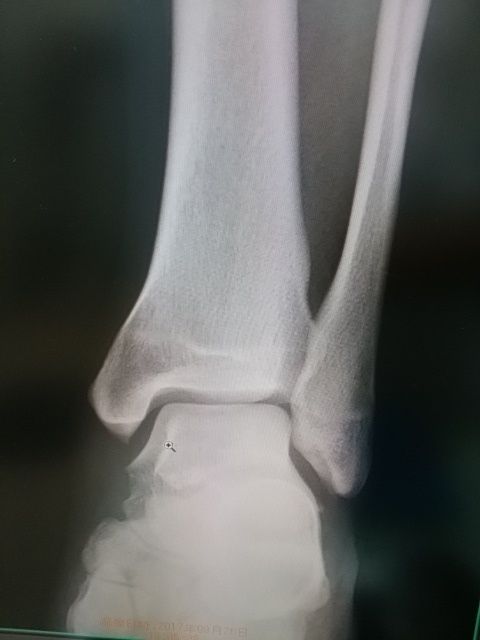

最近、この骨折を良くみかけます

指の中でも、難治性である

マレット骨折

ピンによる手術適応ですが、

保存的に加療すれば、感染のリスク

や痛みもなく、骨癒合を経験します。

拘縮や運動障害も認めないことが

多いですね、